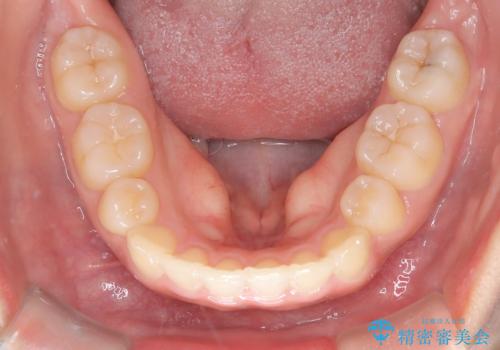

- 前歯のでこぼこが気になると来院されました。

奥歯の噛み合わせは綺麗に噛んでいたため、前歯の叢生(でこぼこ)を、短期間で治療完了するように計画しました。